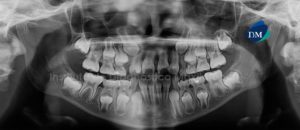

Paciente masculino de 15 años de edad que es referido para la evaluación de los terceros molares. La radiografía panorámica nos muestra la presencia de